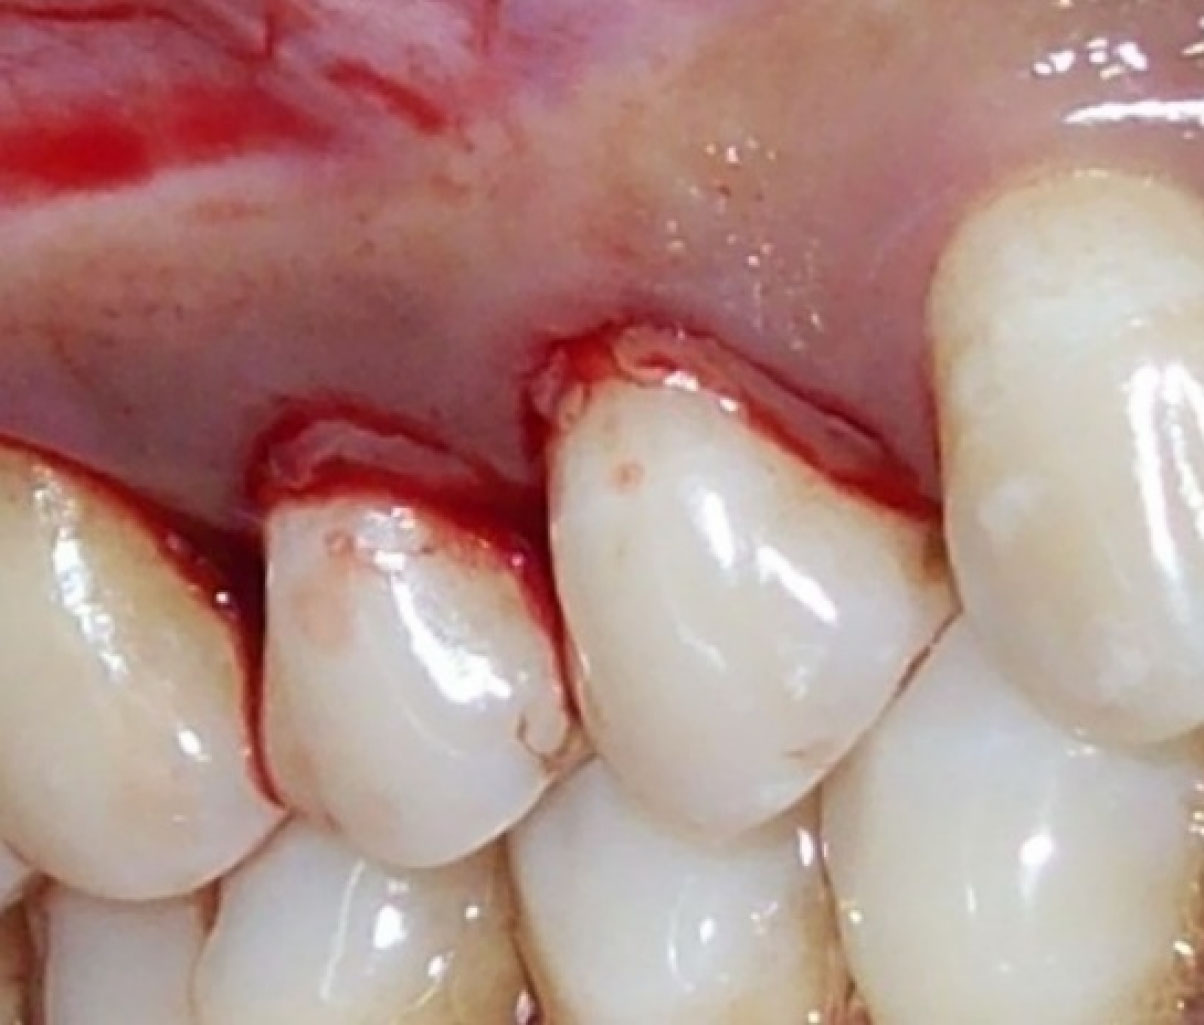

Figure 2. Incision; the control group.

Control sites ( and ) were treated with MWF and sham application of DL therapy, whereas test sites underwent MWF and active DL application. In all the sites, the MWF was followed by SRP and elimination of granulation tissue using hand and power-driven instruments. Before each irradiation episode, a power meter (Fieldmaster, Coherent, Alburn, USA) was used, which allowed the adjustment and standardization of the amount of energy used. For test sites, a DL (wavelength = 940 nm, power = 1 W, tip diameter = 400 µm, power density = 796 W/cm2) was used in continuous mode to remove visible epithelium from the undersurface of the flap. The DL irradiation was carried out at a 45º angle to the soft tissue for 10 seconds from the coronal to apical aspect in parallel paths, followed by 30 seconds of interruption. The charing layer, which was produced due to laser application, was removed with moist gauze. A second laser application (LLLT) was carried out on all the surfaces of the flap (under and outer, exposed bone, and exposed root structures) in continuous mode at 0.1 W, adding up to a total dose of 4 J/cm2 per surface (). The flaps were sutured with 3-0 black silk sutures. Ibuprofen with a 200-mg dose was prescribed every eight hours for five days for pain control. Furthermore, patients were requested to avoid brushing in the treated area for two weeks. They resumed full oral hygiene and function after two weeks.